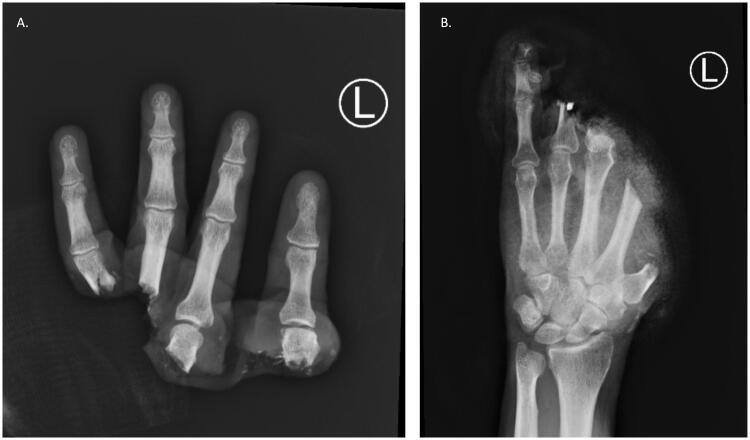

In hand trauma, the uninjured forearm has been touted as the ideal site for ectopic banking in digit/hand amputations. Here, we describe the temporary ectopic implantation and subsequent replantation of a partially amputated hand and highlight the "" - Recovery, Rehabilitation, and Revision over the first year of recovery.

在手部创伤中,未受伤的前臂一直被视为手指/手部截肢后异位储存的理想部位。在此,我们描述了部分离断手的临时异位植入及后续再植情况,并着重介绍了恢复第一年的“恢复、康复及修复”情况。